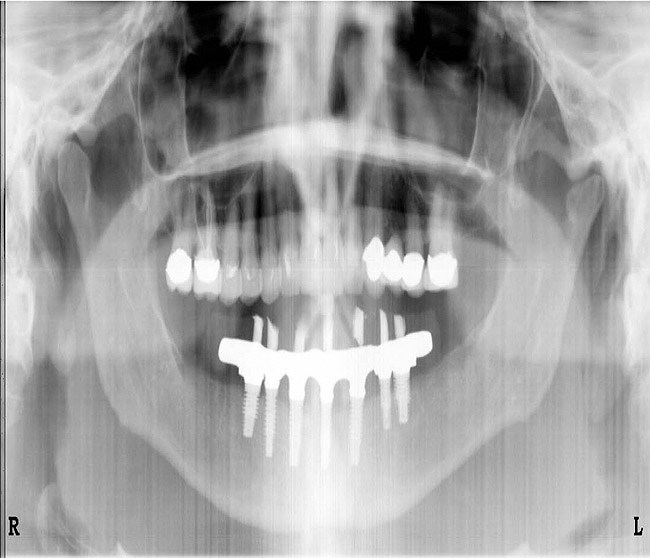

There are two treatment plans for a patient with advanced periodontal disease—one is set by the general practitioner, and the other is set by the periodontist—and for both of them to work as they should, communication must be open and often. They should look at radiographs together, plan treatment together, and set both short- and long-term goals for the patient.

Figure 3   A crown height space < 15 mm necessitates a PFM material selection.

Figure 3